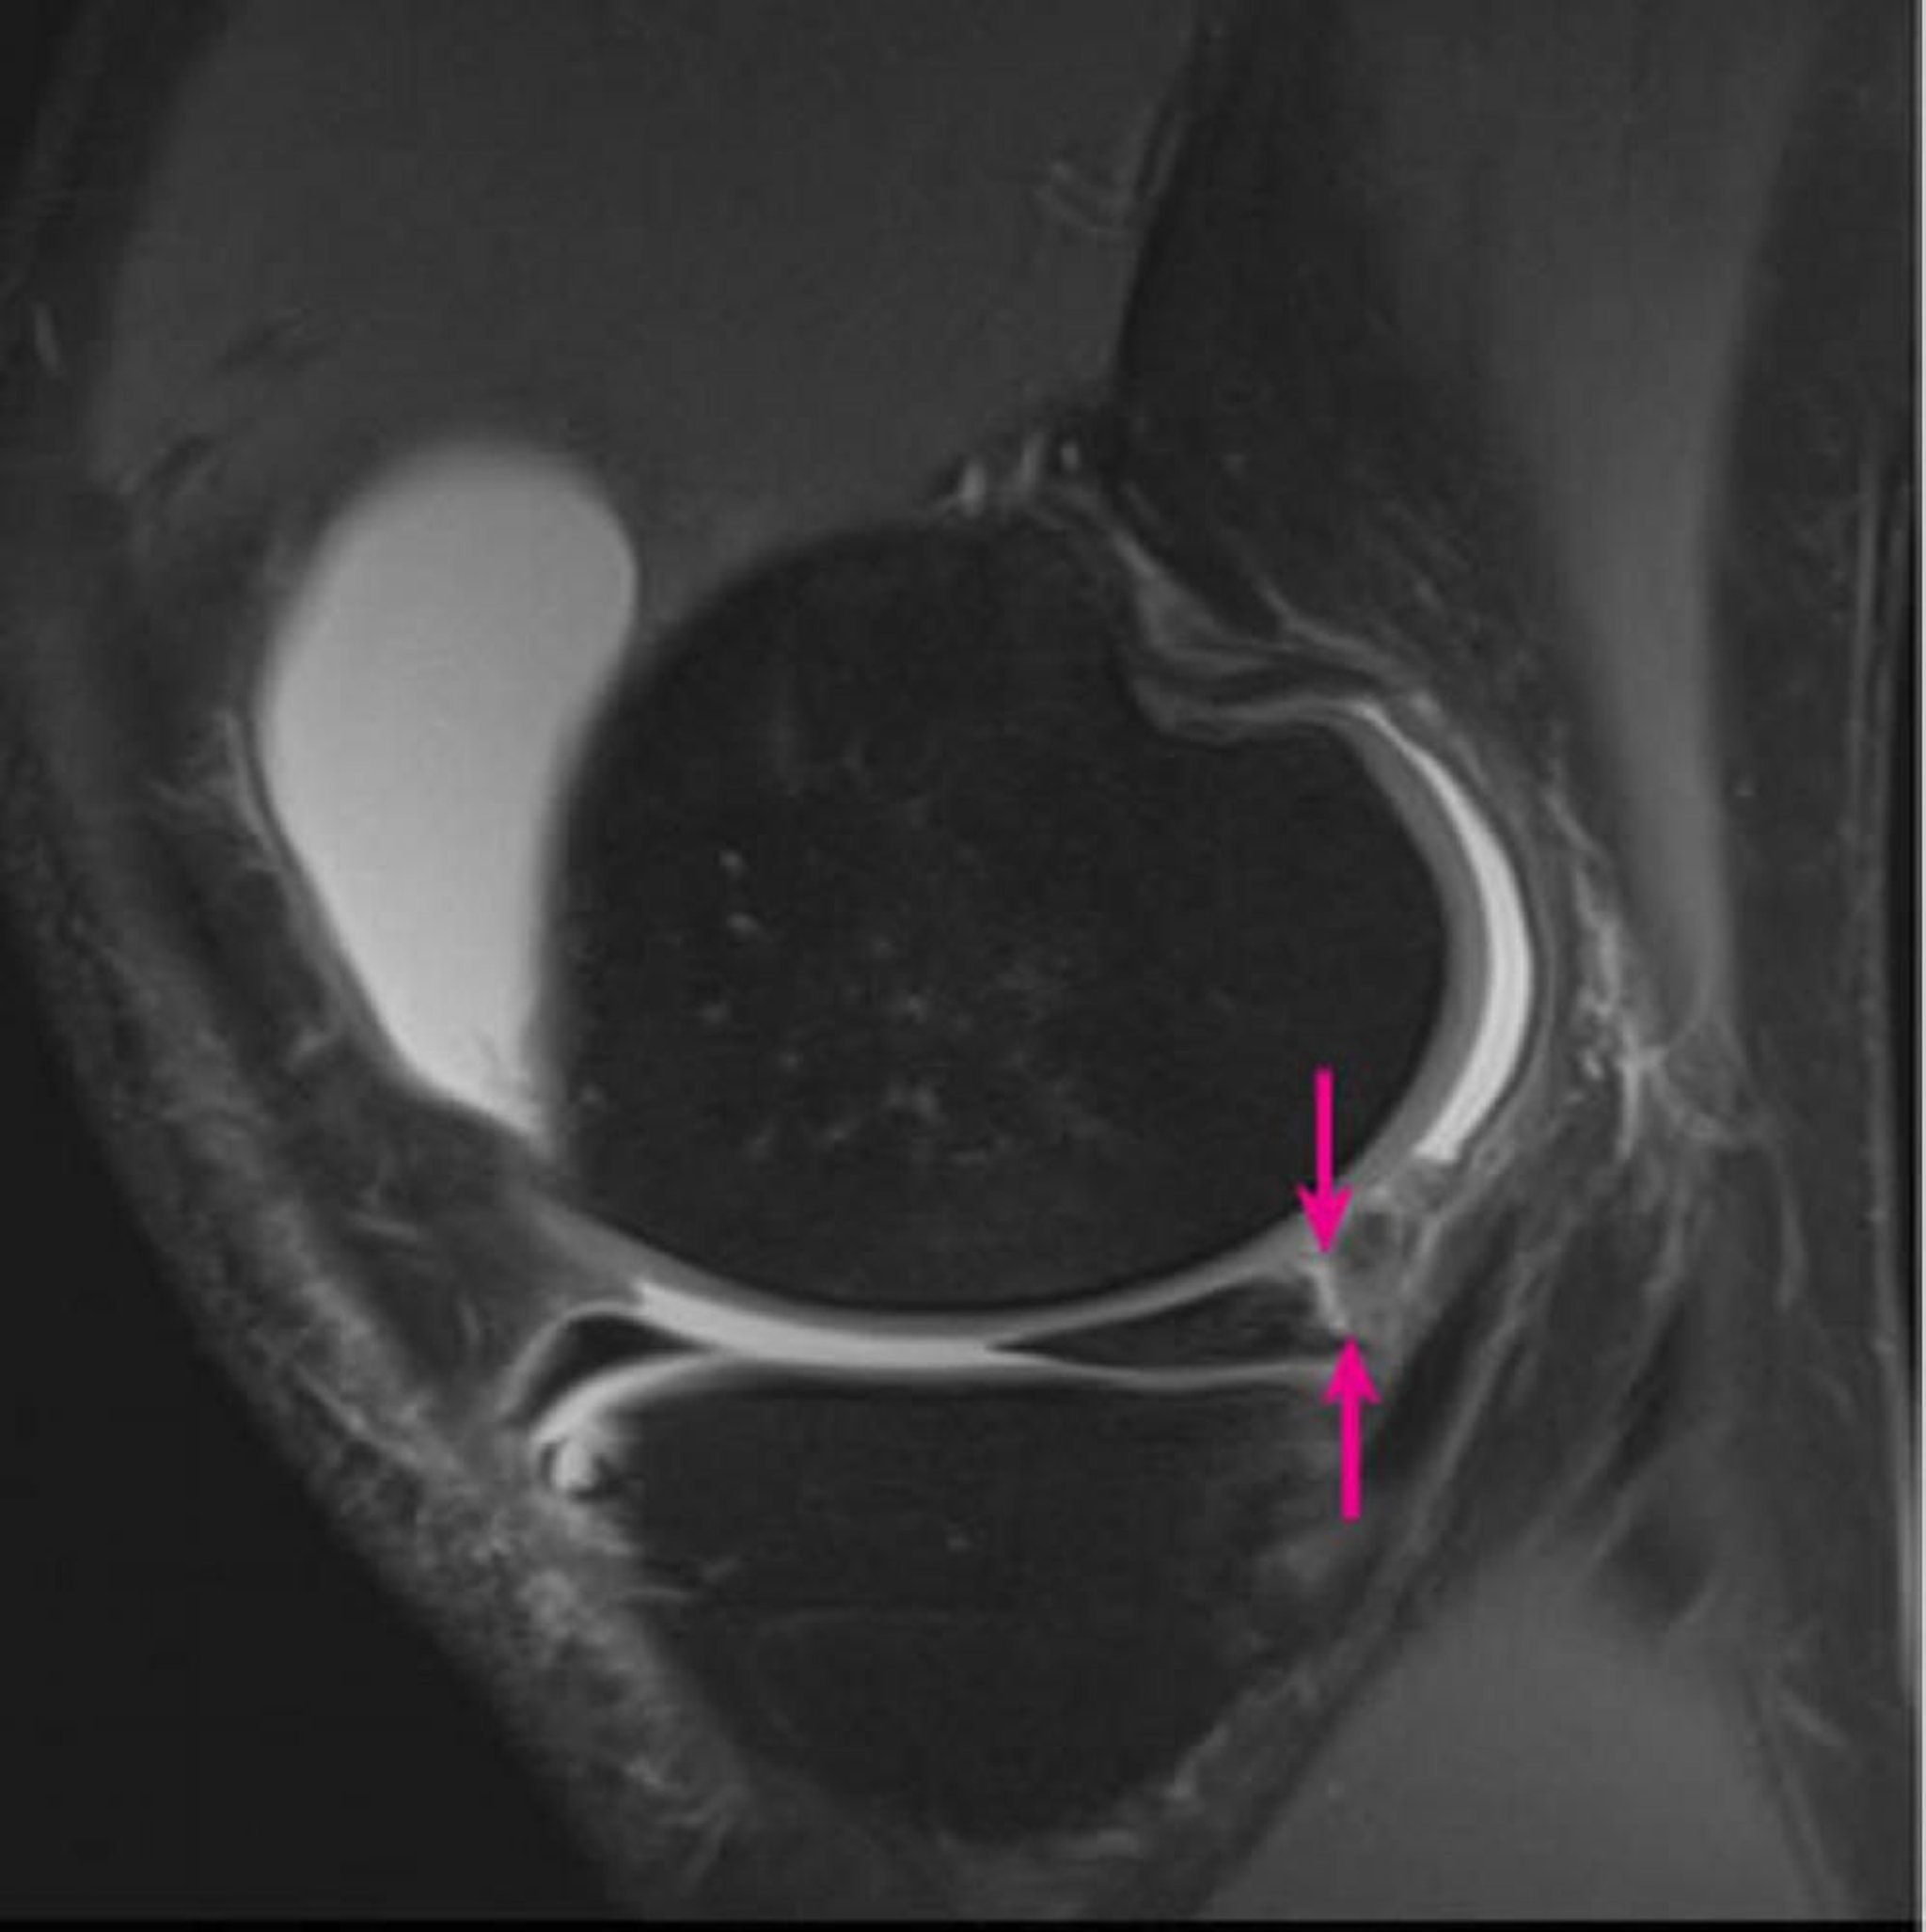

この右膝関節の3テスラMRIプロトン密度強調矢状断像では,内側半月後角でmeniscocapsular separation(矢印)が認められる。

Image courtesy of Hakan Ilaslan, MD.